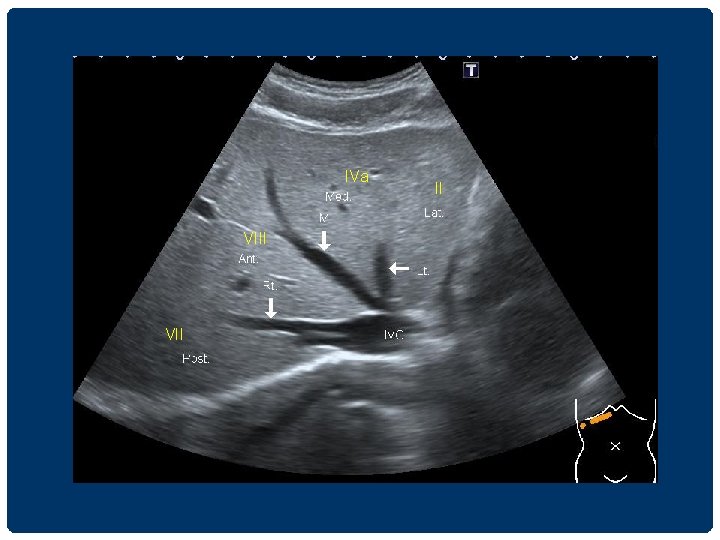

IVa VIII VII II

MHV RHV LHV